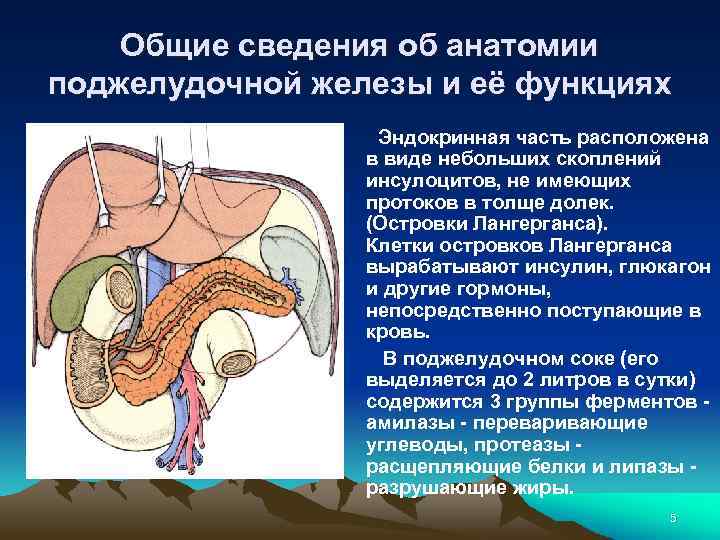

Общие сведения об анатомии поджелудочной железы и её функциях Крупная пищеварительная железа (весом до 100 г у взрослого человека) обладает внешнесекреторной и эндокринной функциями. Расположена она в забрюшинном пространстве, в верхней части живота, лежит поперечно по отношению к позвоночнику на уровне 1 и 2 -го поясничных позвонков. 3

Общие сведения об анатомии поджелудочной железы и её функциях Ткань поджелудочной железы имеет альвеолярнотрубчатое строение, она разделена соединительной тканью на дольки. В последних расположены ацинусы - клетки вырабатывающие поджелудочный сок. Протоки долек сливаются в более крупные и, наконец, в общий выводной проток. 4

Общие сведения об анатомии поджелудочной железы и её функциях Эндокринная часть расположена в виде небольших скоплений инсулоцитов, не имеющих протоков в толще долек. (Островки Лангерганса). Клетки островков Лангерганса вырабатывают инсулин, глюкагон и другие гормоны, непосредственно поступающие в кровь. В поджелудочном соке (его выделяется до 2 литров в сутки) содержится 3 группы ферментов - амилазы - переваривающие углеводы, протеазы - расщепляющие белки и липазы - разрушающие жиры. 5